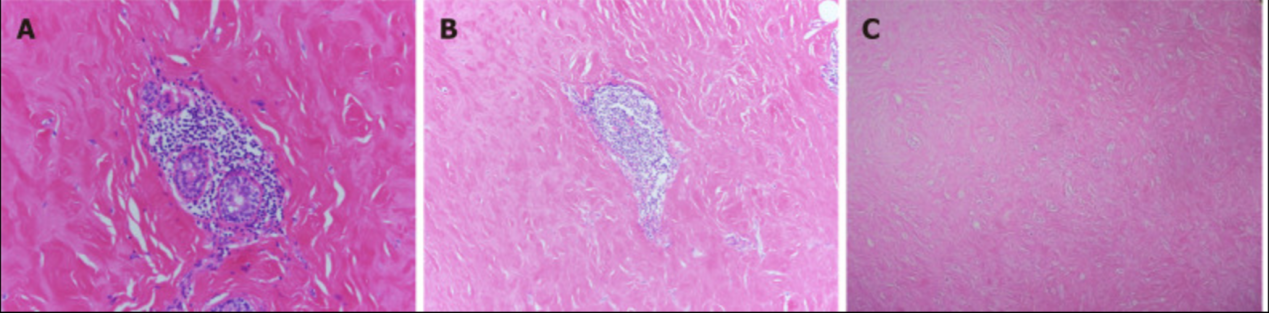

大体解剖显示右乳病变9cm× 8cm× 3cm大小,中间灰红色,1cm× 0.5cm× 0.5cm。剩余的乳腺组织呈灰白色,柔软。左乳病变4cm× 2.5cm× 2.2cm,灰白色,质地柔软。组织病理学结果显示小叶周围有密集的淋巴细胞浸润,周围基质广泛纤维化,上皮样肌成纤维细胞(图4)。诊断为糖尿病性乳腺病。

图4